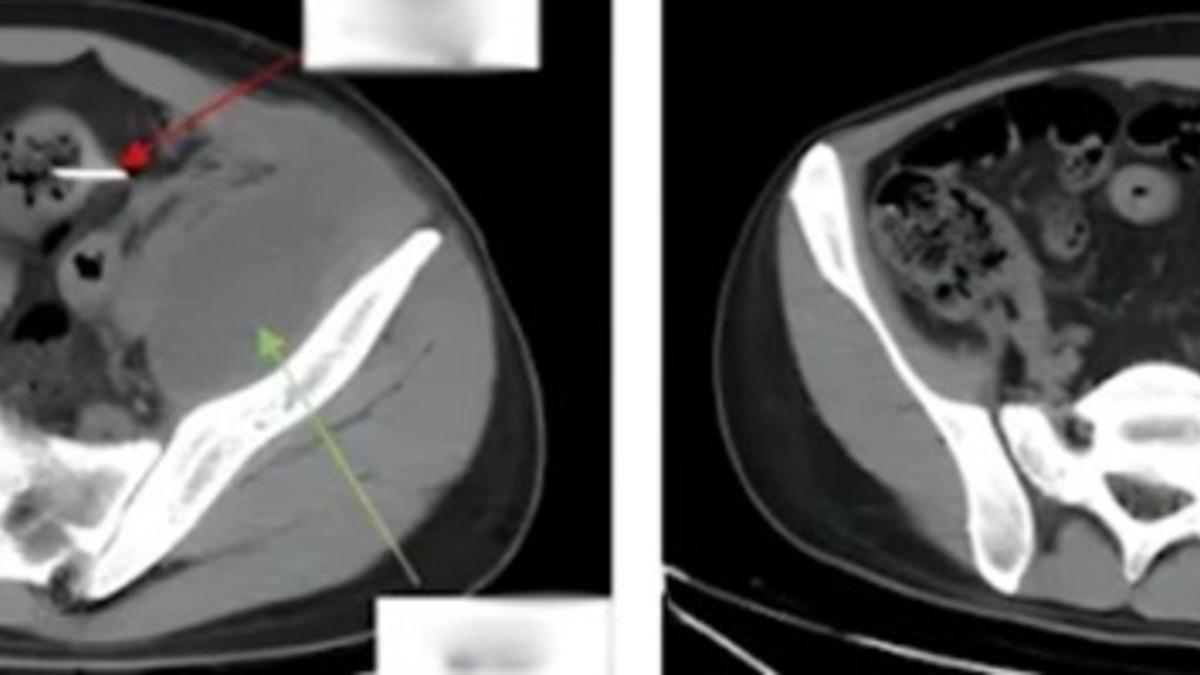

Hastanede röntgen çekildikten sonra sol karın boşluğunun bağırsak duvarında sivri uçlu yabancı bir cisim tespit edildi. Bu cismin iltihaplanmaya ve bağırsak delinmesine neden olduğu ortaya çıktı. Uzun süredir devam eden enfeksiyon 180 mililitre irin üretmişti, bu yüzden doktorlar 2 saat 40 dakika süren laparoskopik bir ameliyat gerçekleştirdiler ve yabancı cismi çıkartmayı başardılar.

Yabancı cismin 13 cm uzunluğunda çöp şiş olduğu tespit edilirken 28 yaşındaki hasta ameliyattan iki gün sonra yeniden yürüyebildi. 5 gün sonra hastanede daha rahat hareket edebildi. 16 gün sonra hastaneden taburcu edildi.